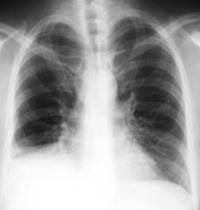

Technology used to diagnose the problem can

include chest x-rays, lung function tests, blood

work and oxygen tests, lung biopsy and other

| | Chest X-rays and |

| | CAT scans